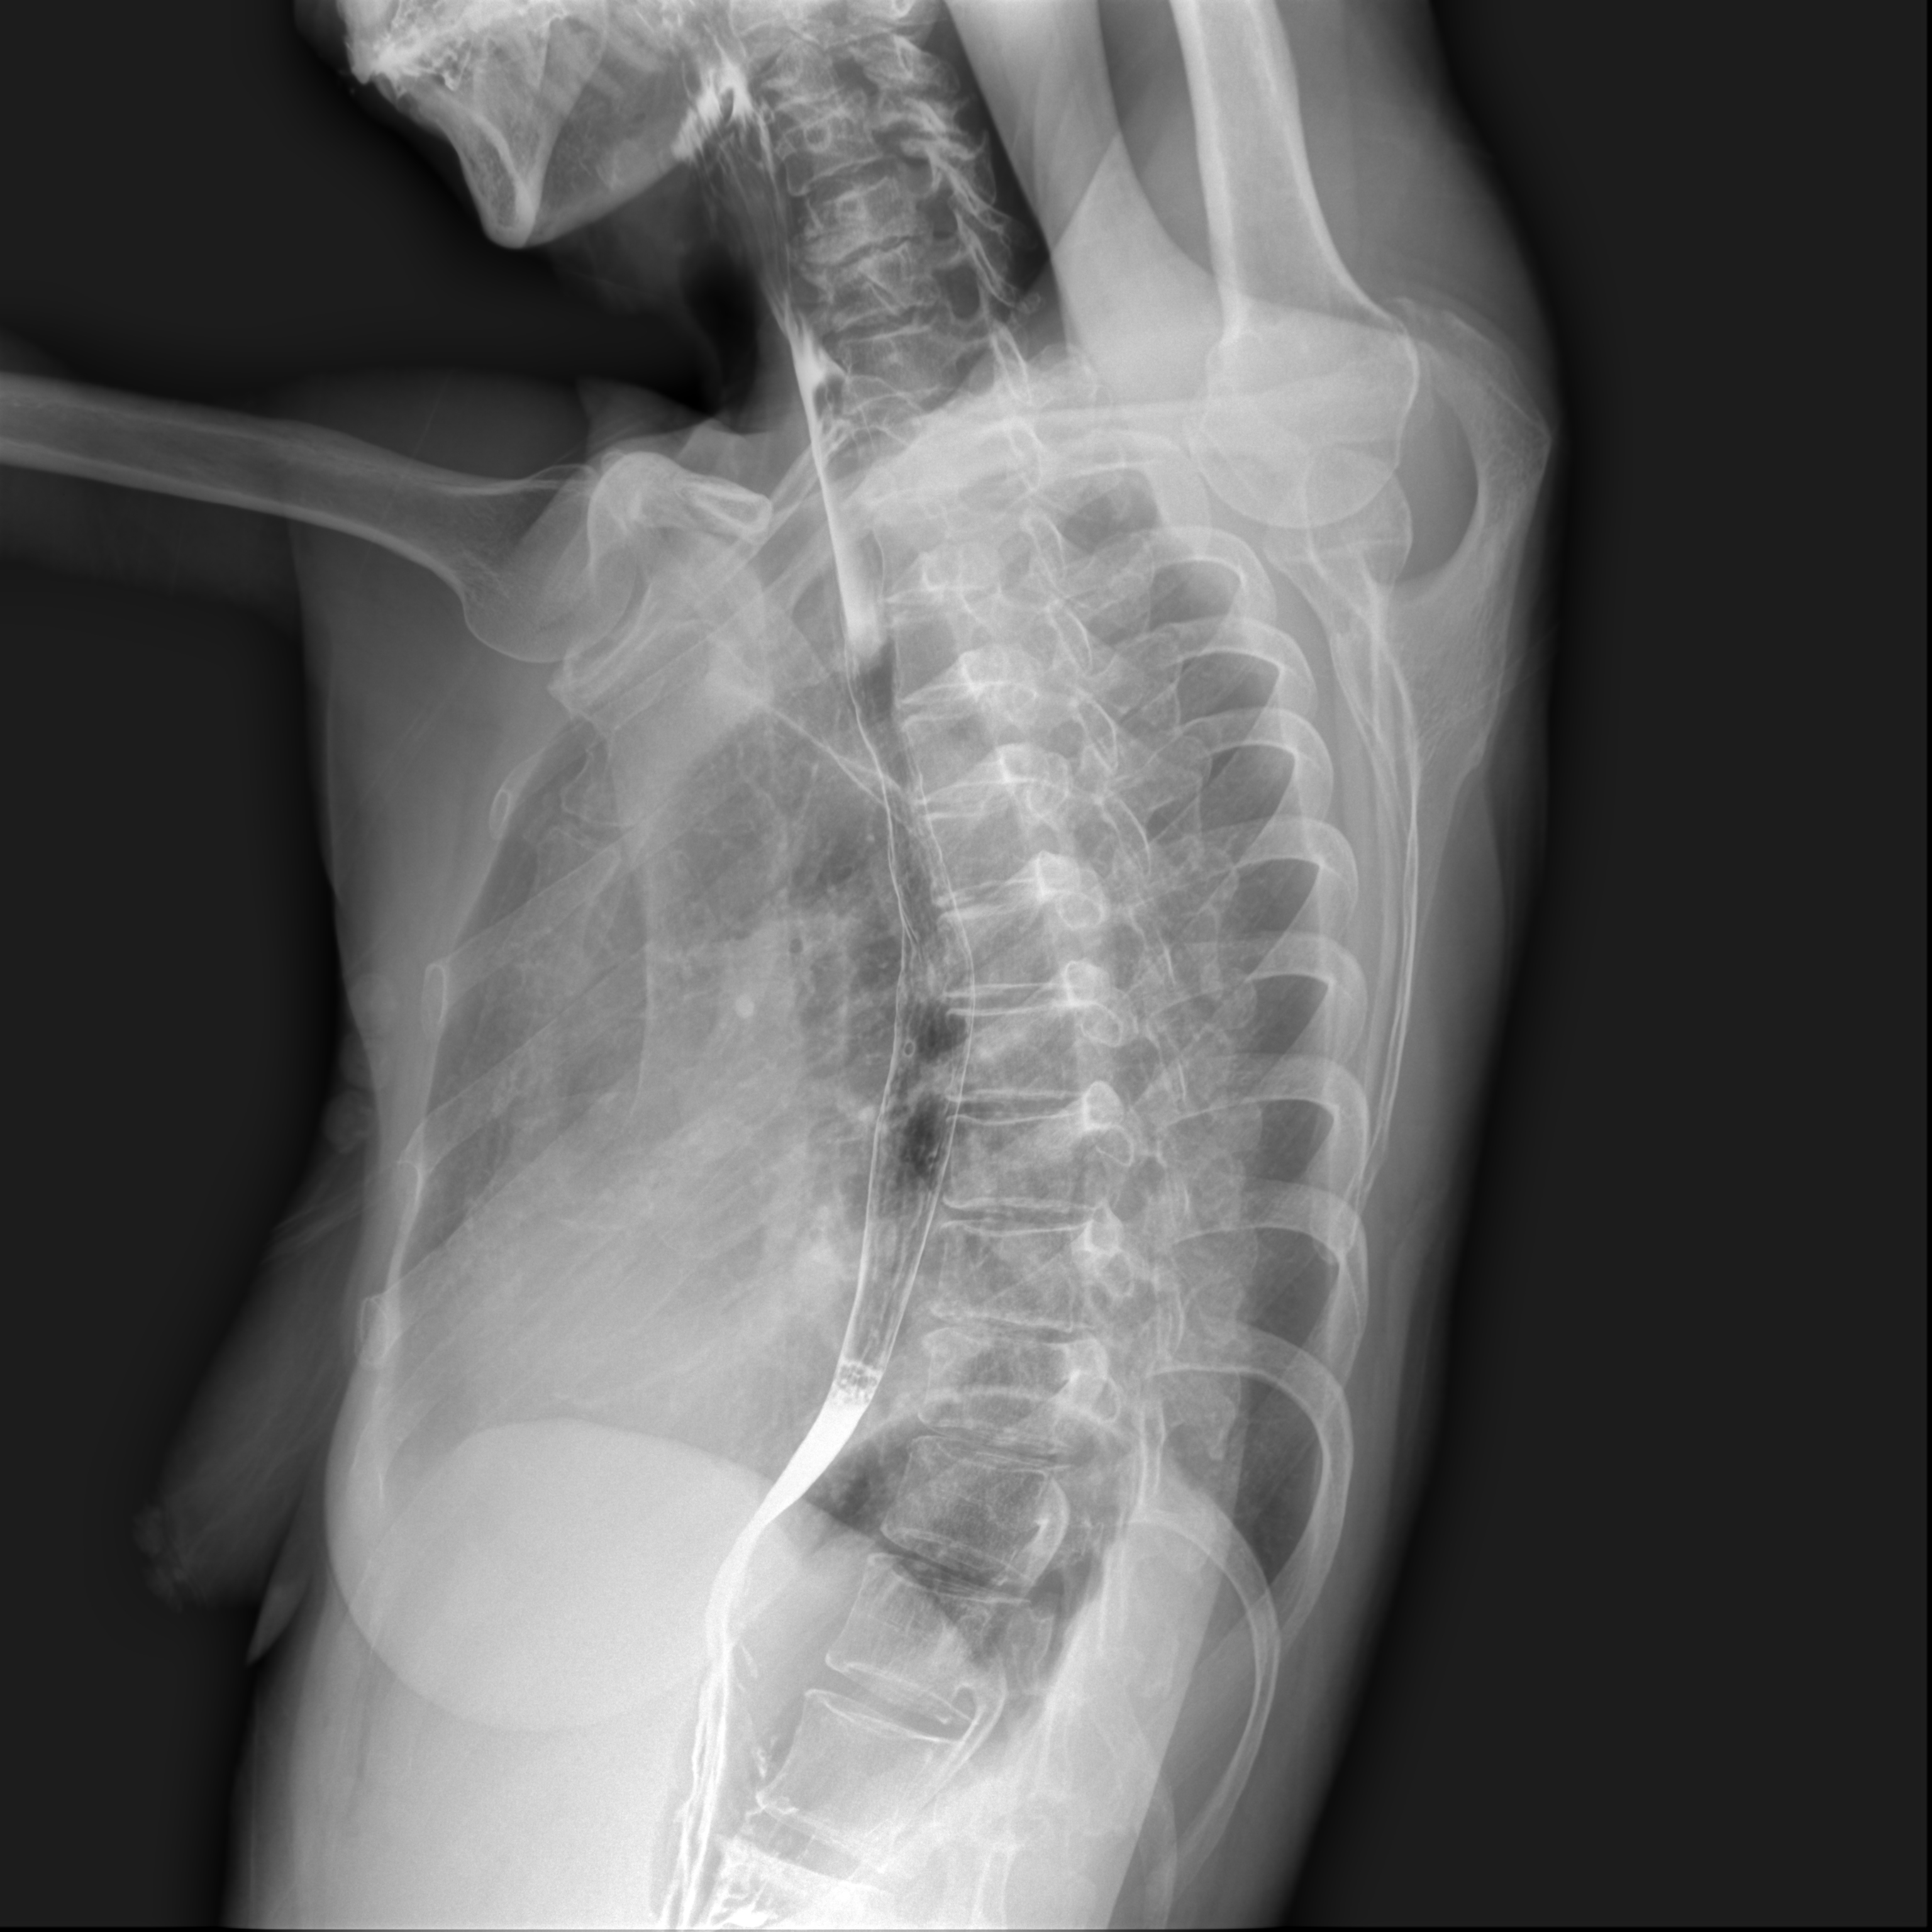

临床图片

腰